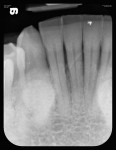

A 78-year-old male patient presented with a history of oral cancer of the right parotid gland that necessitated its removal more than 25 years ago. This resulted in severely restricting the patient’s ability to open wide on his right side (Figure 3). Consequently, it would be difficult, if not impossible, to use a rigid sensor to capture radiographs with this patient. Instead, a flexible phosphor sensor was used to capture the necessary images of the patient’s dentition with no difficulty or discomfort (Figure 4 through Figure 8).